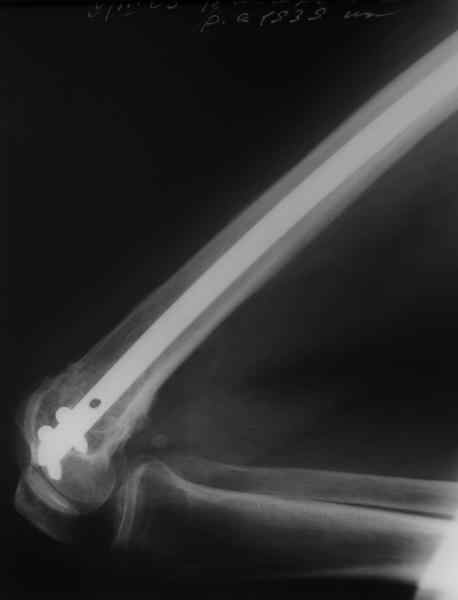

Отправитель: Alexander Chelnokov 20 Февраль 2009, 18:28

Это результат через полгода. К сожалению, пациент больше не приезжал на контрольный осмотр.